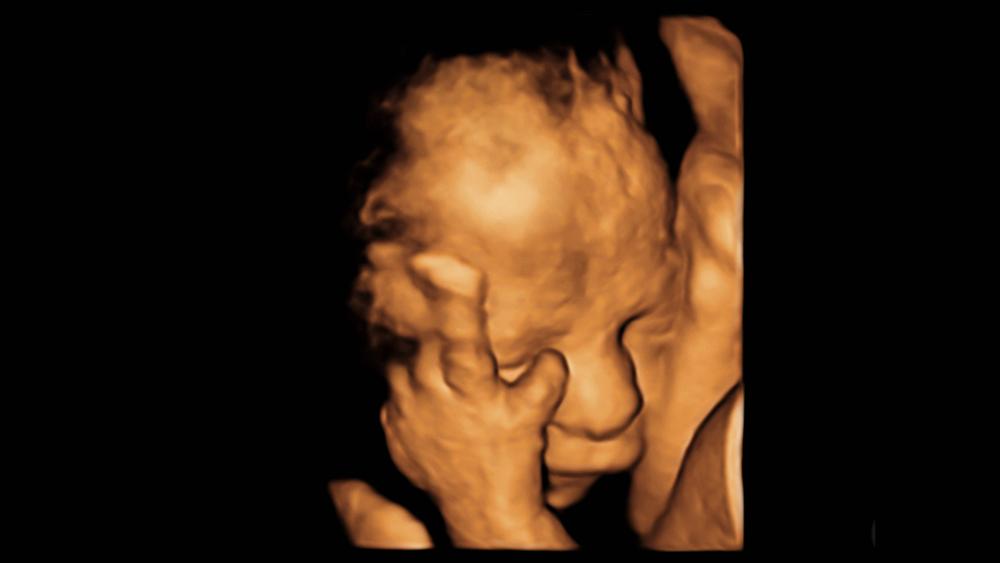

TALLAHASSEE, Fla. (AP) — Republicans in the Florida House of Representatives early Thursday approved a ban on abortions after 15 weeks, moving to tighten access to the procedure ahead of a U.S. Supreme Court decision that could limit abortion rights in America.

The GOP-controlled House passed the 15-week abortion ban after several hours of debate between Democrats who said the measure would impose an unnecessary burden on women and Republicans who said they were protecting the unborn.

Florida's bill contains exceptions if the abortion is necessary to save a mother’s life, prevent serious injury to the mother or if the fetus has a fatal abnormality. The state currently allows abortions up to 24 weeks of pregnancy.